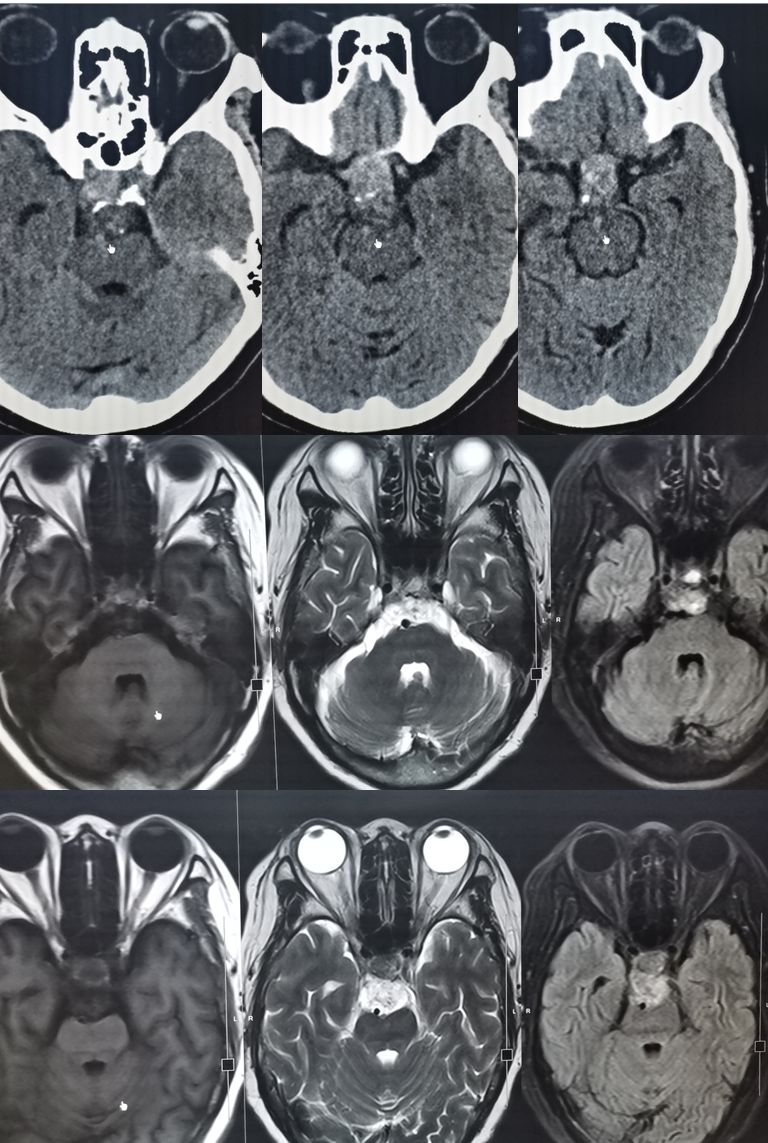

男,29岁,言语不清,协调不良以及行走不平衡3周。

答案:*洛因海**海绵状白质脑病。*洛因海**海绵状白质脑病(heroin spongiform leukoencephalopathy,HSLE)是因烫吸或静脉注射*洛因海**而引起的中枢神经系统器质性疾病。临床和影像特点如下:

1. 有吸*洛因海**史;

2. 急性或亚急性起病;

3. 小脑受损为首发症状,进一步加重可出现锥体系及锥体外系受损表现,甚至昏迷、去皮层状态,但感觉系统不受累;

4. CT和MRI影像显示病灶位于脑白质区,呈广泛、对侧性损害(小脑半球、脑干、内囊后肢、胼胝体压部及大脑半球后2/3),其中小脑受累严重,小脑中线两旁、边界清楚的对侧性类圆形或蝴蝶样病灶最具特点(蝶翼征);在脑干部位,若同时有红核及网状结构受累,则可见“蟹钳征”;在内囊后肢则呈“八字征”。病变在T1W为低信号,T2WI为高信号,FLAIR为高信号,且增强扫描一般无强化.5.病理显示脑白质空泡样变。